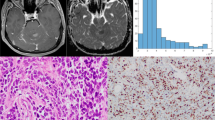

In this retrospective study, we evaluated the distribution of absolute and normalized ADC values of medulloblastomas. Tumors were manually segmented and diffusivity metrics calculated on a pixel-by-pixel basis. We calculated a variety of first-order histogram metrics from the ADC maps, including entropy, minimum, 10th percentile, 90th percentile, maximum, mean, median, skewness and kurtosis, to differentiate molecular and histological variants. ADC values of the tumors were also normalized to the bilateral cerebellar cortex and thalami. We used the Kruskal–Wallis and Mann–Whitney U tests to evaluate differences between the groups. We carried out receiver operating characteristic (ROC) curve analysis to evaluate the areas under the curves and to determine the cut-off values for differentiating tumor groups.

Results

We found 65 children with confirmed histopathological diagnosis of medulloblastoma. Mean age was 8.3 ± 5.8 years, and 60% (n = 39) were male. One child was excluded because histopathological variant could not be determined. In terms of medulloblastoma variants, tumors were classified as classic (n = 47), desmoplastic/nodular (n = 9), large/cell anaplastic (n = 6) or as having extensive nodularity (n = 2). Seven other children were excluded from the study because of incomplete imaging or equivocal molecular diagnosis. Regarding medulloblastoma molecular groups, there were: wingless (WNT) group (n = 7), sonic hedgehog (SHH) group (n = 14) and non-WNT/non-SHH (n = 36). Our results showed significant differences among the molecular groups in terms of the median (P = 0.002), mean (P = 0.003) and 90th percentile (P = 0.002) ADC histogram metrics. No significant differences among the various medulloblastoma histological variants were found.